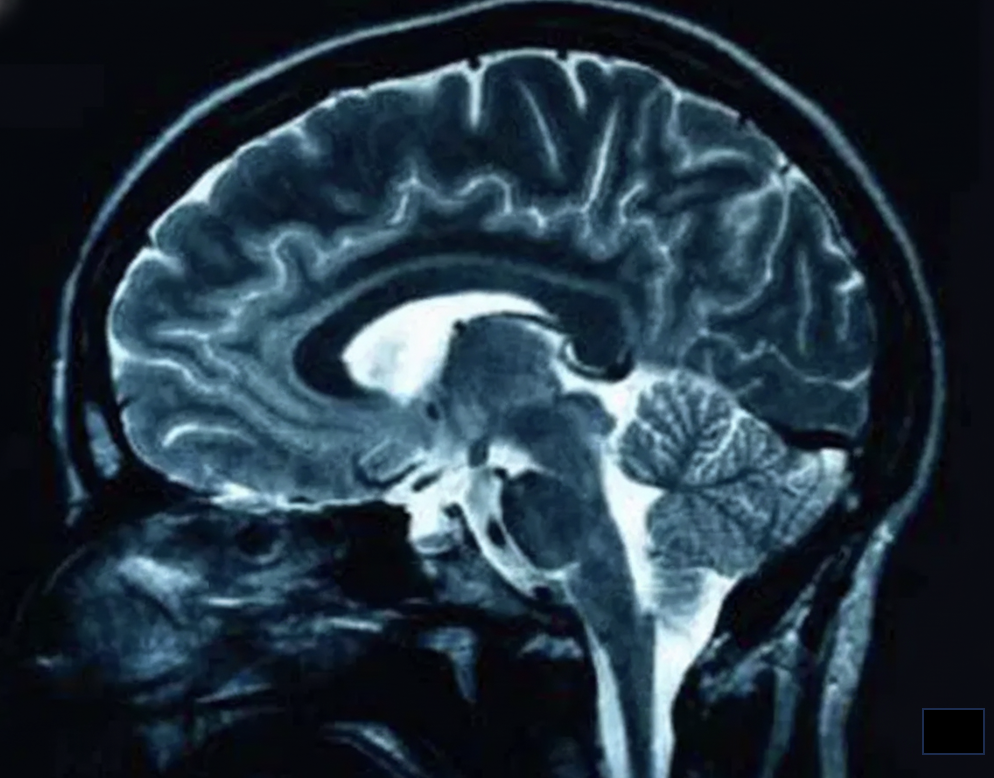

Automated, accurate, and reproducible brain structure analysis from MRI scans. AtrofiQ provides objective data for neurological assessment and research.

AtrofiQ processes T1-weighted MRI scans to deliver automated brain volume analysis, cortical thickness mapping, and normative database comparisons. AI-generated reports present critical data points with percentile-based summaries, enabling clinicians to assess neurological conditions with precision and confidence.